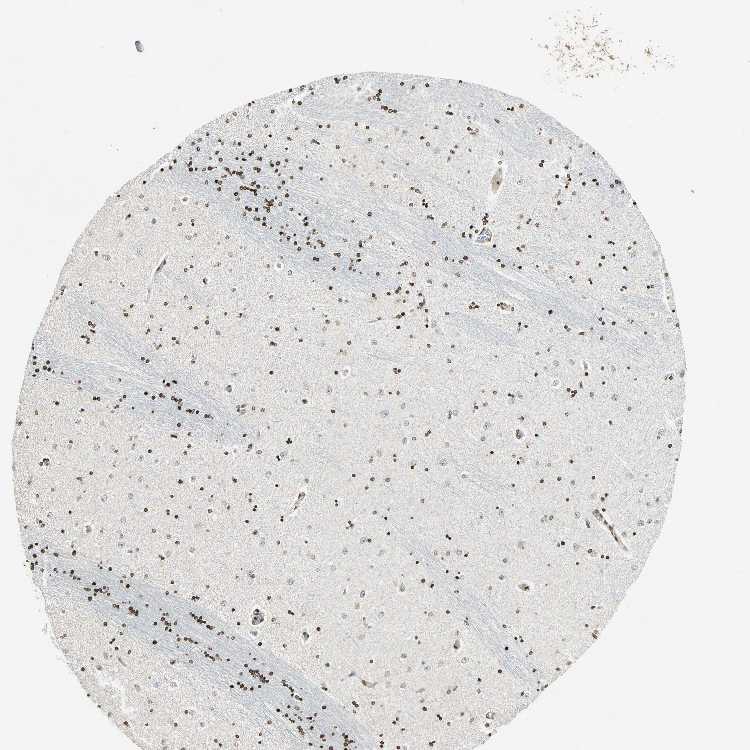

HIPPOCAMPUS - Antibody stainingi

Antibody staining in the annotated cell types in the current human tissue is reported as not detected, low, medium, or high, based on conventional immunohistochemistry profiling in selected tissues. This score is based on the combination of the staining intensity and fraction of stained cells.

Each image is clickable and will lead to virtual microscopy that enables deeper exploration of all samples and also displays staining intensity scores, fraction scores and subcellular localization as well as patient and tissue information for each sample.

Antibody HPA003162Antibody CAB005191

Glial cells Not detectedMedium

Neuronal cells LowLow